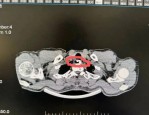

61岁张阿姨误吞鸡骨致食道穿孔,多学科联合救治转危为安警示囫囵吞咽风险

张阿姨 61 岁,因误吞鸡骨而致使食道穿孔。后经宁波市医疗中心李惠利医院多学科联合进行救治,这才让她转危为安。 当时就想着喝点水,然后吃点东西咽下去。真的完全没料到...